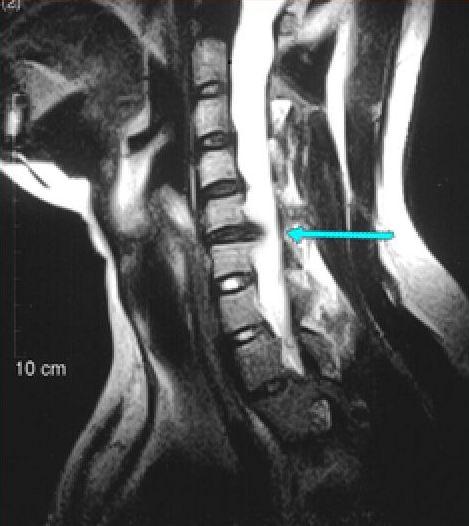

上面科普示意图可能不是很清晰,下面上个颈椎间盘突出患者的MRI示意图,可以清晰的看到脊髓受到了严重的压迫。

骨科的检测,类似下图这种。(我在2014年底就拍了X光片显示颈椎变直,然而当时的医生却没重视,后来重复走了很多冤枉路,所以碰上一个好医生也是不容易……)